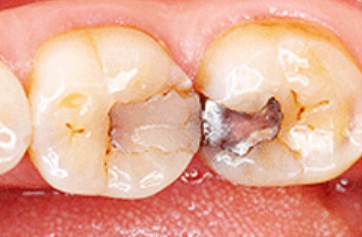

치아의

썩은 부위가

넓은 경우